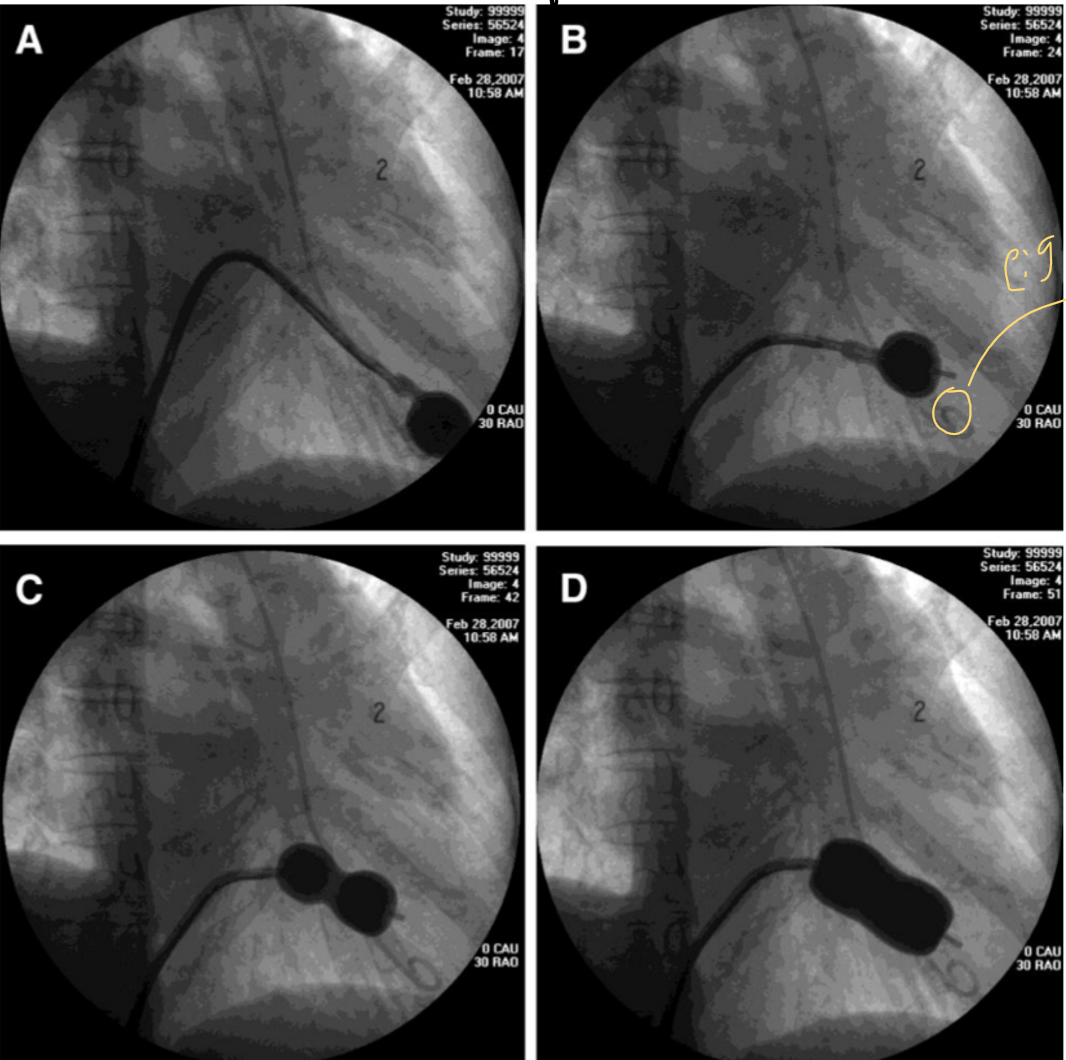

what is occurring here

Mitral Stenosis

what is occurring in this image

Balloon mitral valvuloplasty

MS

WHAT PROCEDURE IS HAPPENING

MITRAL VALVULOPLASTY

to treat mitral stenosis the **** balloon must go *****

Inoue balloon must go transseptal

an INOUE balloon is used to treat what

mitral valve stenosis